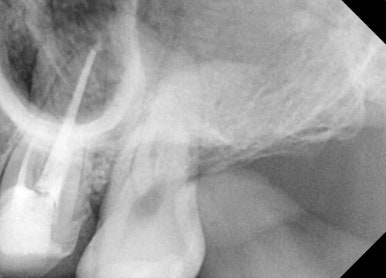

📸 케이스 2: #16 4-Canal Re-Endo

✅ 치료 후 통증 사라짐